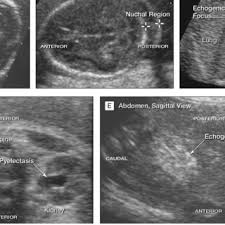

Soft Markers Fetal Ultrasound